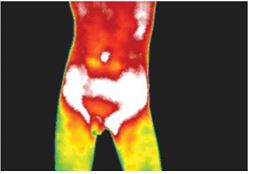

自閉症小孩大多有大腸有問題,如下圖:

熱像圖的顏色代表溫度。白色最嚴重。白色最热 - 比正常皮肤温度高3°C

红色第二高,高于正常皮肤温度2 C,正常皮肤温度是绿色。